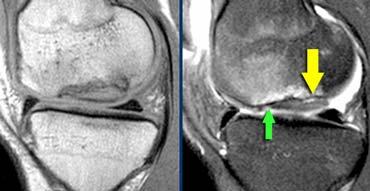

TRÁI: Các bó sợi ACL có hướng bình thường nhưng không bám vào lồi cầu đùi. PHẢI: Dấu hiệu hõm rỗng: dịch áp sát mặt trong lồi cầu ngoài.

Đôi khi dễ đánh giá hơn liệu các bó sợi có còn bám vào xương hay không khi quan sát trên mặt phẳng vành.

Tuyệt đối không được có dịch áp sát mặt trong lồi cầu ngoài.

Nếu có dịch ở vị trí này, được gọi là ‘dấu hiệu hõm rỗng’, cho thấy ACL đã bị bong khỏi điểm bám trên lồi cầu đùi.

Trên mặt phẳng ngang có dấu hiệu hõm rỗng (mũi tên vàng) ở vị trí lẽ ra ACL phải bám vào lồi cầu. Ở mức thấp hơn (sang phải), ACL đứt đã dính sẹo vào PCL (mũi tên xanh lá).

Trên mặt phẳng ngang cũng phải thấy dây chằng nằm sát bên lồi cầu.

Ở mức thấp hơn, chúng ta thấy ACL đứt bám dính vào dây chằng chéo sau.

Chúng đã dính vào nhau thành sẹo.

Đây là hình ảnh rất thường gặp trong đứt ACL mạn tính.

Sự dính sẹo này tạo ra góc gấp cấp tính của dây chằng.

Mặc dù ACL đã dính vào PCL, nhưng vẫn không đủ vững và cần phải tái tạo.